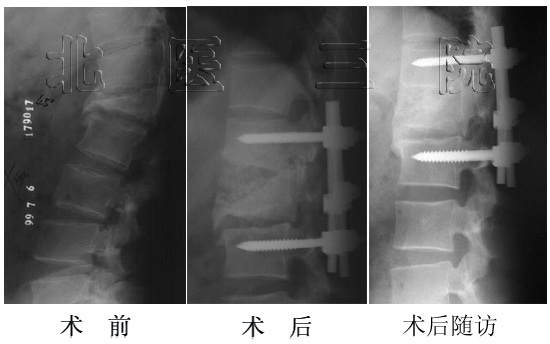

某女,25岁,因腰痛入院.2002.5行后路峡部裂修补术,术后7月已愈合